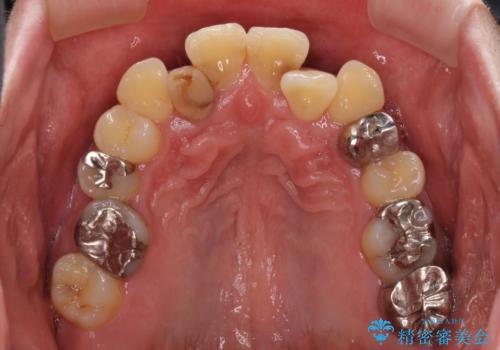

左右下顎の大臼歯は、ともに歯根が破折しており、抜歯が必要な状態でした。

放置したことで炎症による骨吸収が顕著であるため、骨造成を併用してインプラント埋入を行うこととしました。

咬み合わせは受け口傾向であり、上顎前歯の叢生が顕著であったことから、第1小臼歯抜歯による矯正治療も検討しましたが、下顎大臼歯を左右ともに抜歯するため、非抜歯による矯正治療を行うこととしました。

矯正治療でインプラント埋入を行い、矯正治療後に気になる前歯と合わせてオールセラミッククラウンによる補綴治療を行うこととしました。